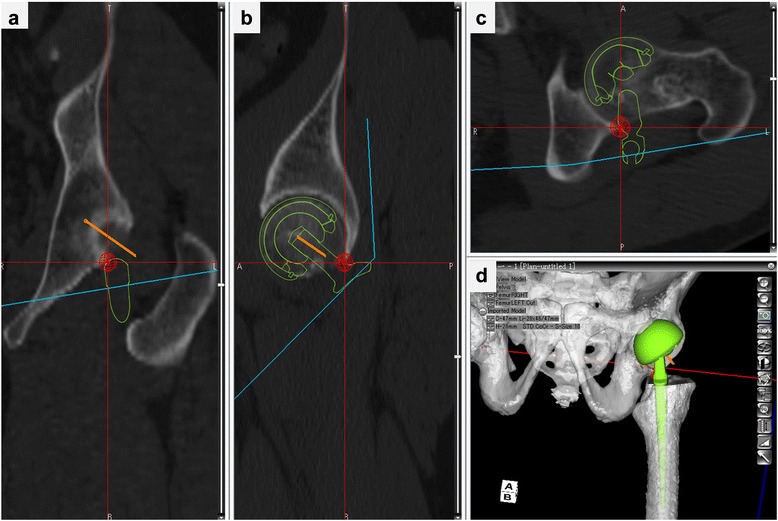

Fig. 1.

3D simulation of hip ROM and detection of impingement site in BHA. Neck of femoral implant impinges on posterior edge of acetabulum in external rotation with 10° extension. a Coronal view. b Sagittal view. c Axial view. d 3D model